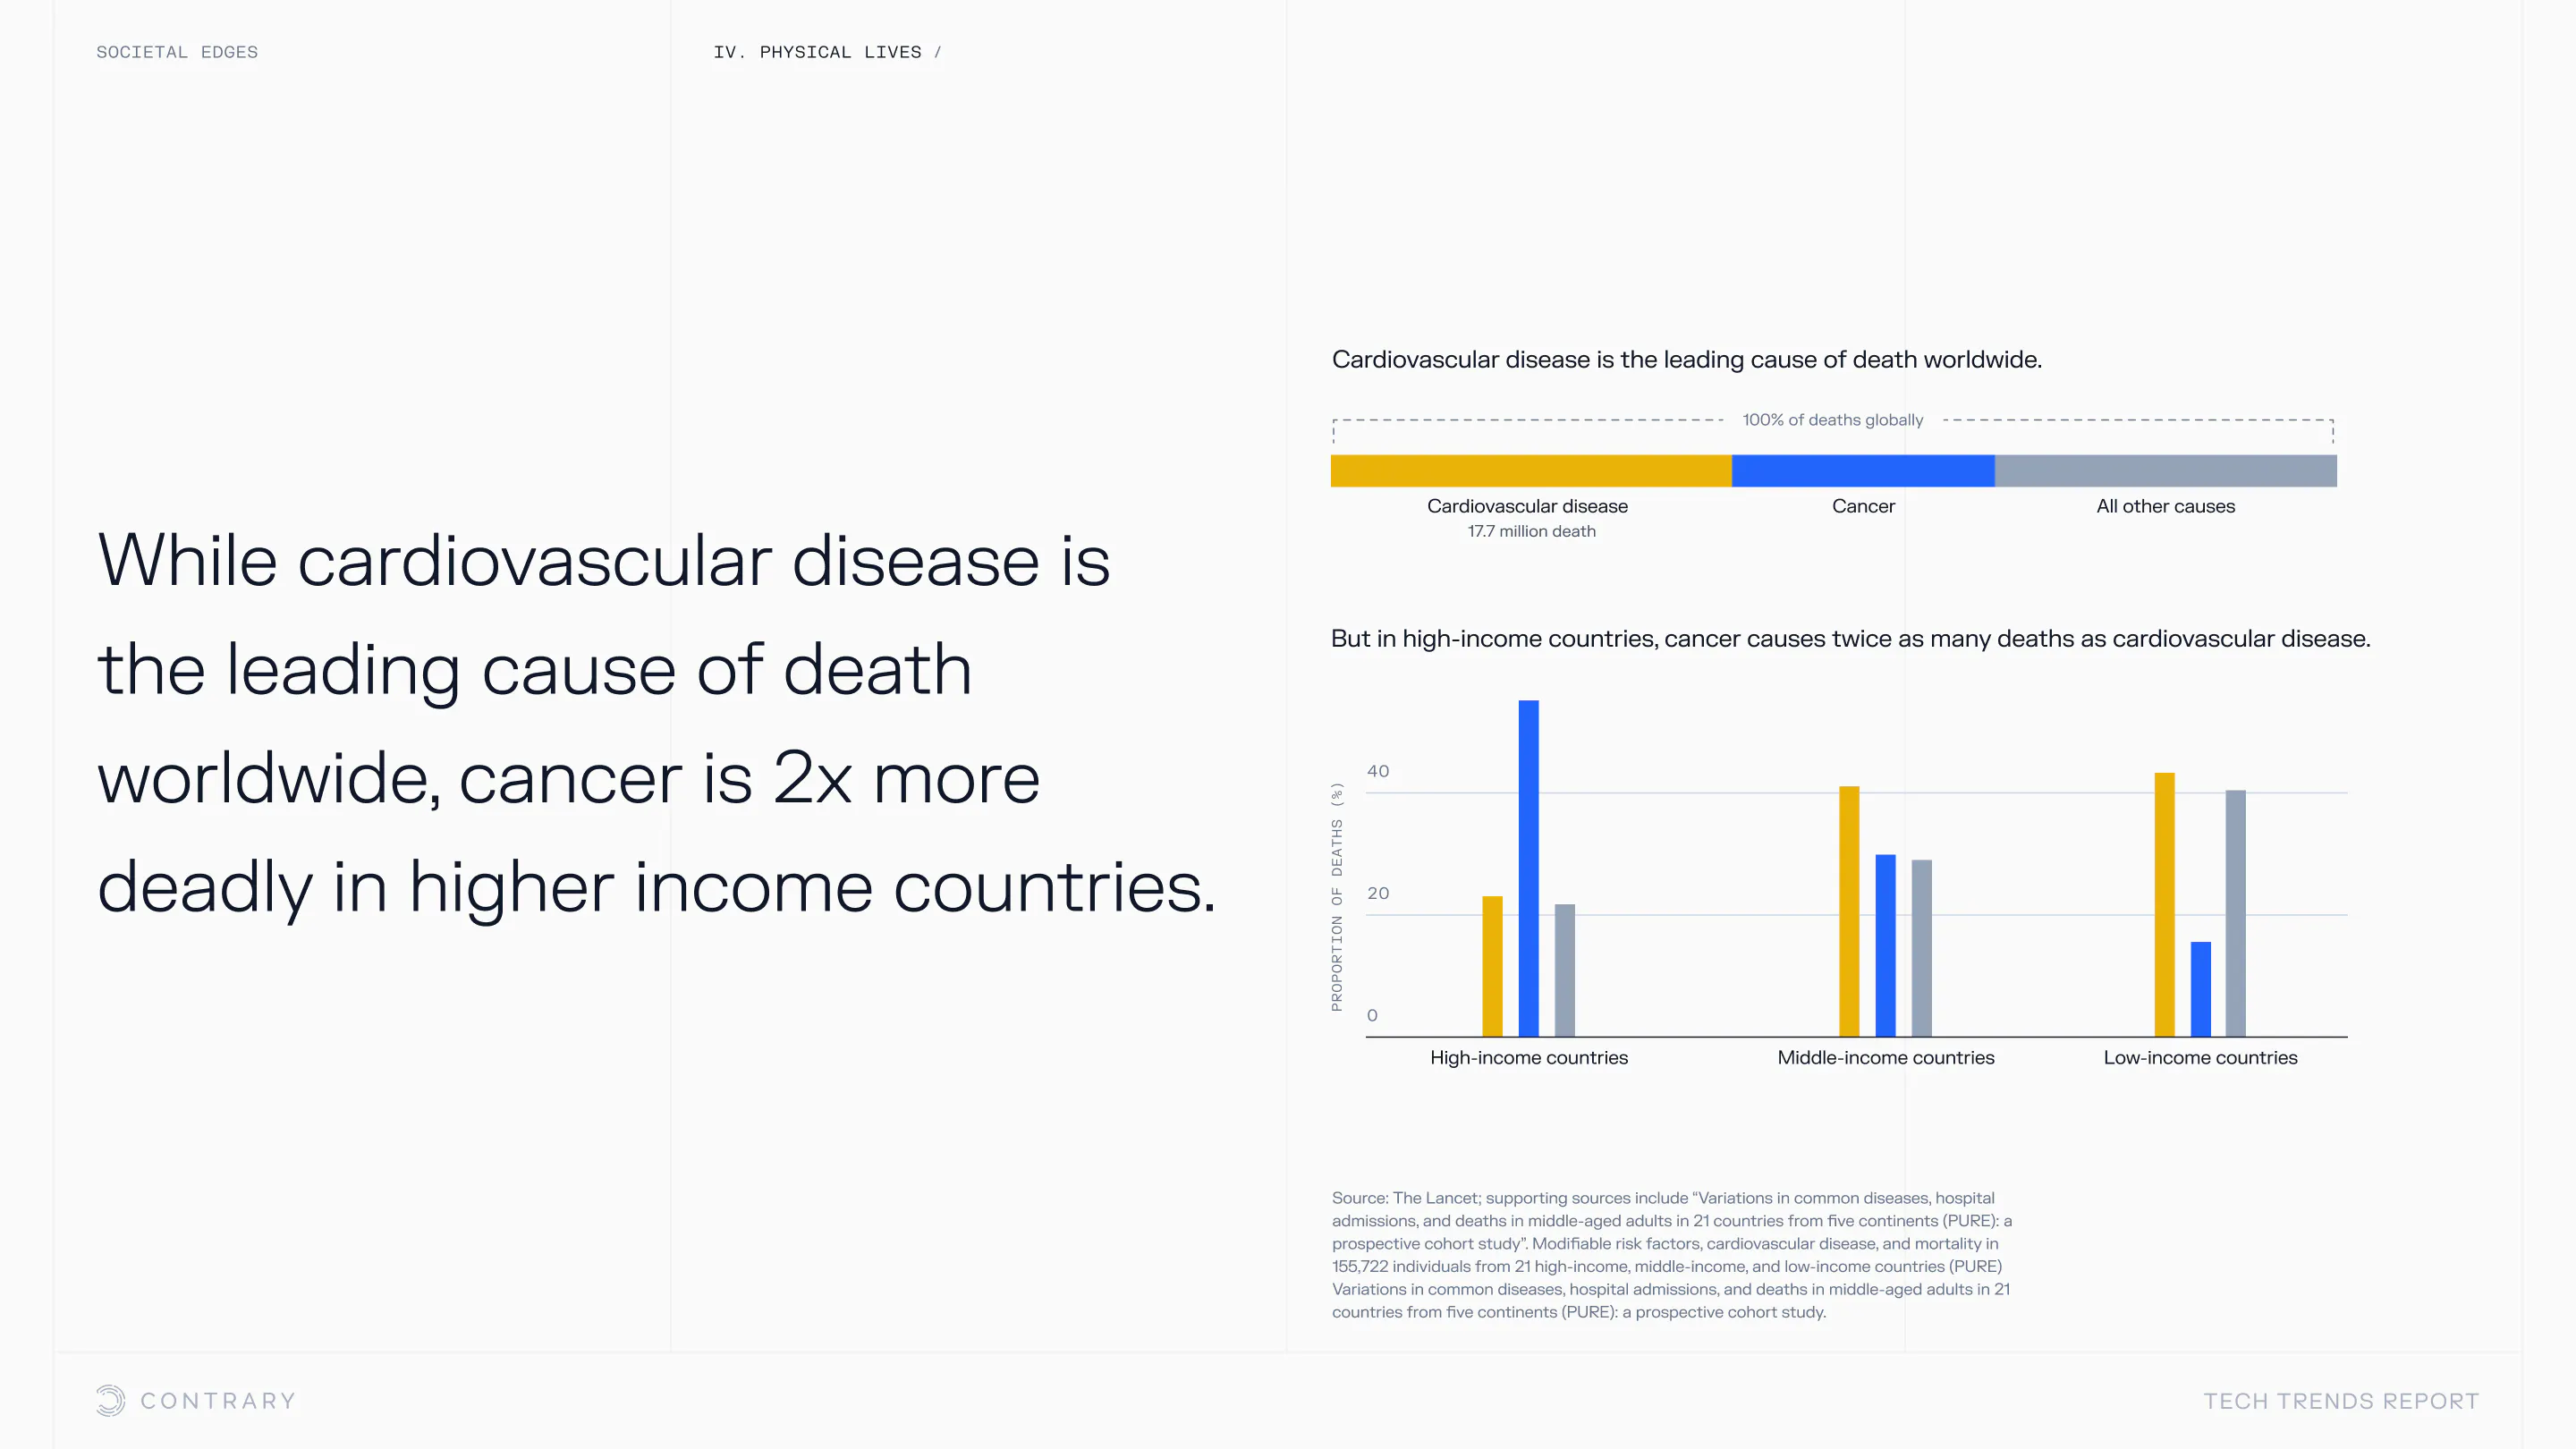

An aging population is bringing up a range of increased concerns, from mental health to disease control. Obesity and gastrointestinal cancers are plaguing younger generations. The cutting edge is tackling a system that has unhealthiness woven into it.